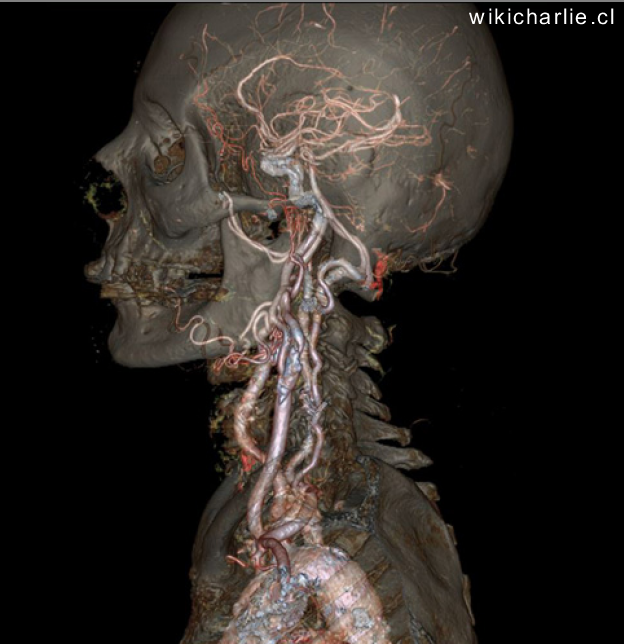

El gran reto: de las neuronas a la conducta

Una proteína verde fluorescente ha permitido trazar las conexiones del cerebro, algo así como el “mapa de carreteras”. “Todas estas conexiones estaban determinadas en el ratón e incluso en humanos. Pero lo que no estaba bien determinado era en qué cantidad estaban interconectados las distintas estructuras del cerebro entre sí.” Este estudio ha permitido “saber dónde estas las autopistas, las carreteras nacionales y las secundarias del cerebro”.

Mapa de las redes neuronales del cerebro de ratón

Un segundo trabajo del Instituto Allen ha logrado por primera vez establecer el mapa de las redes neuronales del cerebro completo de ratón. Hasta ahora se contaba con mapas parciales de conexiones entre distintas regiones del cerebro, pero este es el primer «conectoma» del cerebro completo de un mamífero. Desde hace un cuarto de siglo se dispone del conectoma del gusano C. elegans, que tiene solo 302 neuronas. Sin embargo, el cerebro del ratón tiene 75 millones de neuronas, organizadas de forma similar a las del humano.

Ambos trabajos se han dado a conocer un año después de que Obama hiciera pública la iniciativa Brain. En esta segunda etapa se ha doblado el presupuesto inicial, que era de cien millones de dólares, para dotar a los neruocientíficos de herramientas capaces de desentrañar el funcionamiento del cerebro.